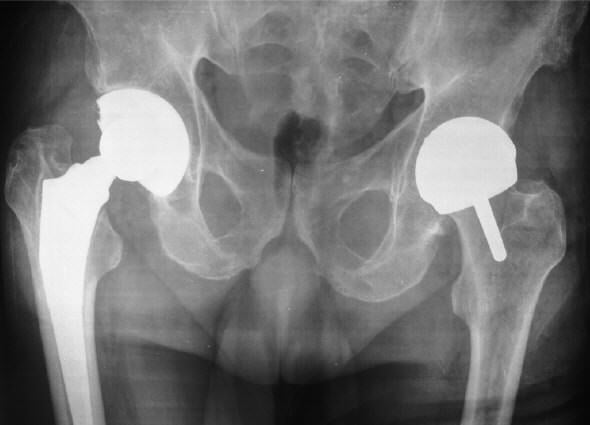

Эндопротезирование бедра

Бедренное – одно из самых важных сочленений организма. Испытывая большие нагрузки или в силу дегенерации, оно может выйти из строя, доставляя своему обладателю сильный дискомфорт и массу ограничений. В германских клиниках уже появились новые разборные протезы, которые позволяют подогнать имплантат до размеров натурального соединения. Такие протезы минимизируют риски вывиха и абсолютно не ощущаются, как инородные тела, во время эксплуатации.

Инвазивность хирургического процесса постоянно уменьшается, а срок службы имплантатов при грамотном обращении и соблюдении всех рекомендаций – неумолимо растет, так как разрабатываются новые методы крепления, точнее, «врастания» протеза в кость и материалы для их изготовления.